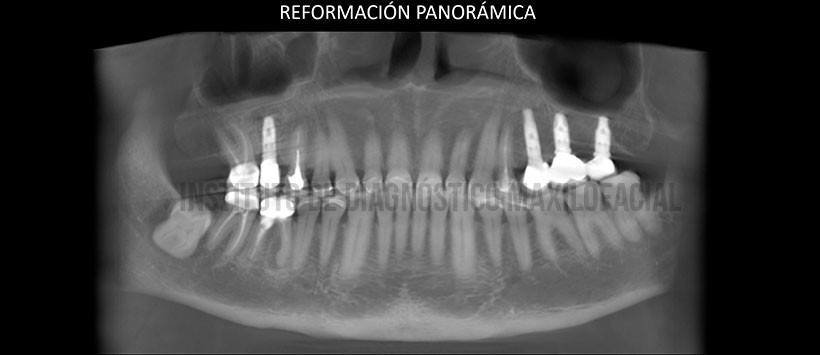

A la evaluación de la radiografía panorámica se evidencian múltiples implantes con prótesis sobre implantes, múltiples coronas protésicas, presencia de material de obturación de conducto en piezas 17 y 47, además de las piezas 15 y 46 material de obturación de conductos, espigos y corona protésica con proceso osteolítico en zona apical. Siendo lo mas resaltante la pieza 48, la cual esta retenida en posición mesioangulada con un aumento de la densidad radicular. (Figura 1)